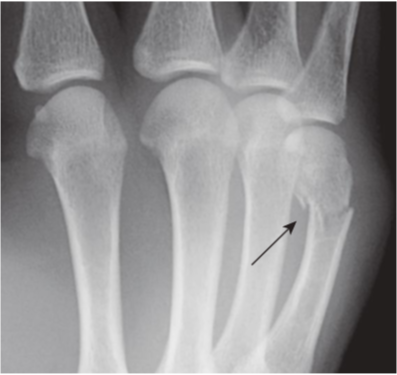

Boxer’s fracture.

A boxer’s fracture is a fracture of the neck of the 5thmetacarpal with palmar angulation of the distal fracture fragment (black arrow). It is most often the result of punching a person. Despite its name, it is not a fracture commonly sustained by professional boxers, whose 2ndand 3rdmetacarpals and radius bear the brunt of the force.